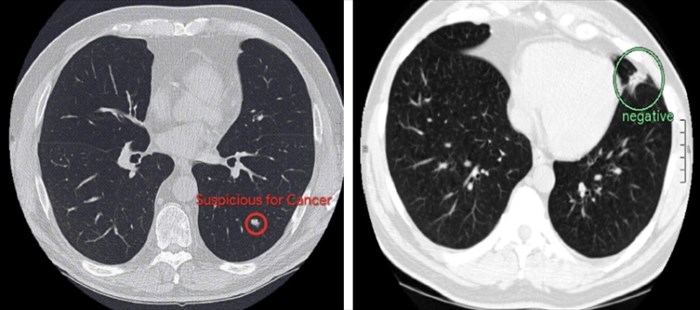

The reason for these issues is that CT scans are comprised of hundreds of 2D images and cancer can be minute and difficult to identify.

The end result? An AI model that can not only produce an overall lung cancer prediction in 3D but also recognise subtle cancerous lung nodules. In addition, the model can intelligently factor in information from previous scans to identify any changes or pick up on the growth rate of suspicious nodules that may be a sign of lung cancer.

When previous CT imaging was available, the AI and radiologists performed comparably. However, when it came to predicting the risk of lung cancer without referencing the patients previous CT scans, the AI algorithms proved to identify malignancies with greater accuracy than the experienced radiologists reviewing the same scans. In these instances, the AI picked up 11% fewer false positives and 5% fewer false negatives.

Google AI scans of the lungs